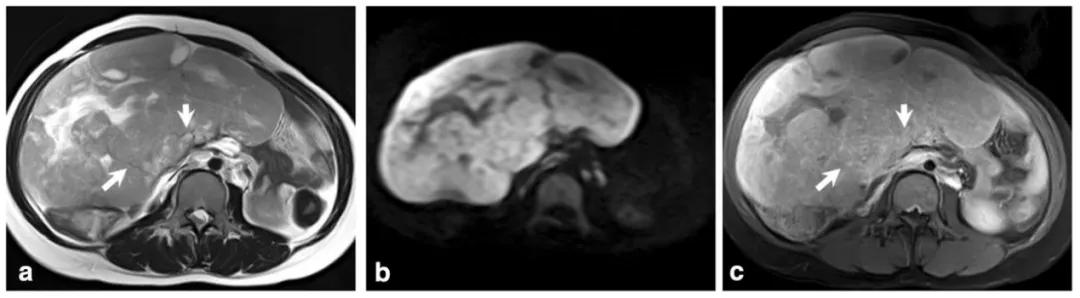

女,22 岁,无性细胞瘤。乳酸脱氢酶及碱性磷酸酶升高。T2WI 示右侧卵巢分叶状肿物(图 a),DWI 呈高信号(图 b),增强扫描明显强化(图 c)。箭头显示肿物内可见纤维血管分隔。